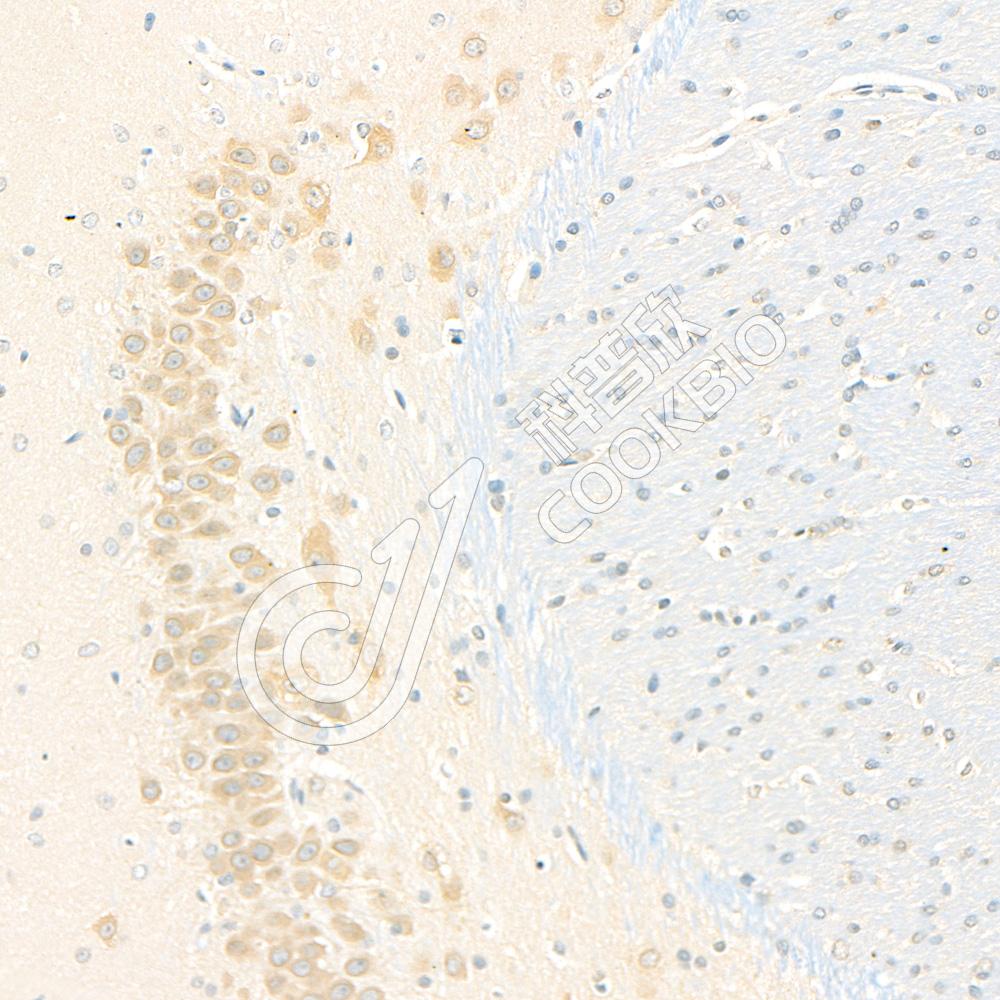

IHC检测GSK3 beta蛋白(货号 K135505).

样品: 小鼠脑, 4%多聚甲醛 (货号KSG1101) 固定12-24小时.

抗原修复: 柠檬酸抗原修复液(干粉, pH 6.0) (KSG1201), 98℃, 20分钟.

—抗: 1: 1800稀释, 4℃ 孵育过夜.

二抗: S-vision免疫组化多聚二抗(山羊抗兔),即用型 (货号KB3906), 室温孵育20分钟.

样品: 大鼠脑, 4%多聚甲醛 (货号KSG1101) 固定12-24小时.